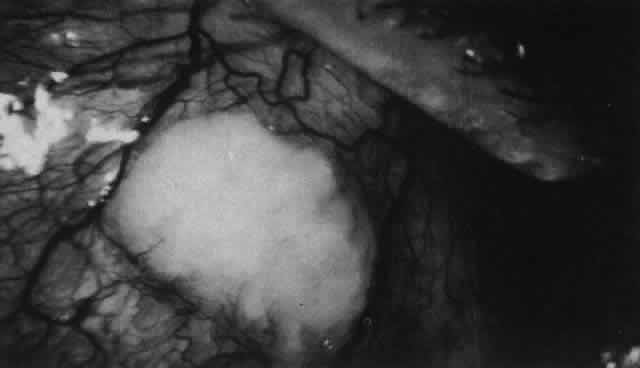

What is clinically represented solely by inflammation and edema is histopathologically

a granulomatous lesion of the sclera, the center of which

consists largely of plasma cells, lymphocytes, and mast cells (Figs. 21 through 23). Foster and colleagues have identified the cellular subsets and glycoproteins

collagen remote from the site of cellular infiltration.  Fig. 21. Advancing edge of a granulomatous reaction. Scleral fibers are split and

separated by edema and then disrupted when invaded by the granuloma Fig. 21. Advancing edge of a granulomatous reaction. Scleral fibers are split and

separated by edema and then disrupted when invaded by the granuloma